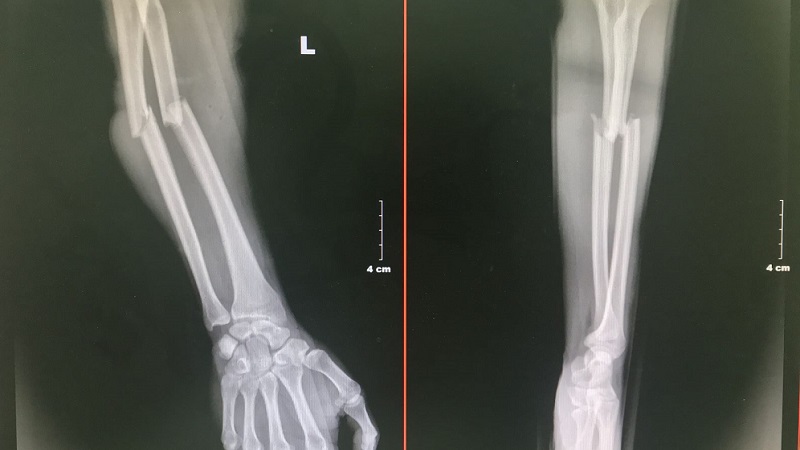

Dựa vào hình thức bên ngoài, gãy xương được phân làm hai nhóm chính là:

Dựa vào hình thái và vị trí vết gãy, giới chuyên gia chia gãy xương thành các loại:

Gãy xương thường xuất hiện ở vùng xương dài của tứ chi, ít phổ biến ở các xương ngắn và xương dẹp nhưng độ nghiêm trọng của dạng sang chấn này lại cao hơn. Khi bị gãy xương, có 2 phương pháp can thiệp được ưu tiên hàng đầu, đó là bó bột kết hợp nắn chỉnh ngoài và phẫu thuật triệt căn. Việc lựa chọn cách thức điều trị nào là tùy vào mức độ, phạm vi ảnh hưởng của dạng chấn thương đang gặp phải.

Đây là trường hợp xương liền lại nhưng bị biến dạng, sai lệch so với tư thế giải phẫu ban đầu. Hiện tượng này thường xảy ra khi không được sơ cứu kịp thời và đúng cách. Ngoài ra nó có thể phát sinh do kỹ thuật can thiệp còn hạn chế hoặc người bệnh không tuân thủ đúng hướng dẫn của bác sĩ chuyên khoa.

Sau khi gãy xương và điều trị thì vết thương sẽ lành, kích thước của xương sau gãy có thể lệch hoàn toàn so với bên đối xứng. Đây là hiện tượng không hiếm gặp và rất dễ xảy ra ở trẻ em. Theo đó, khi vết gãy làm tổn thương đến sụn tăng trưởng thì tốc độ dài xương của hai bên cơ thể sẽ có độ chênh lệch đáng kể. Điều này thể hiện rất rõ ở vùng xương chi, đặc biệt là xương đùi. Khi đó sẽ dẫn đến tình trạng đi lại khó khăn do chân bị tập tễnh.